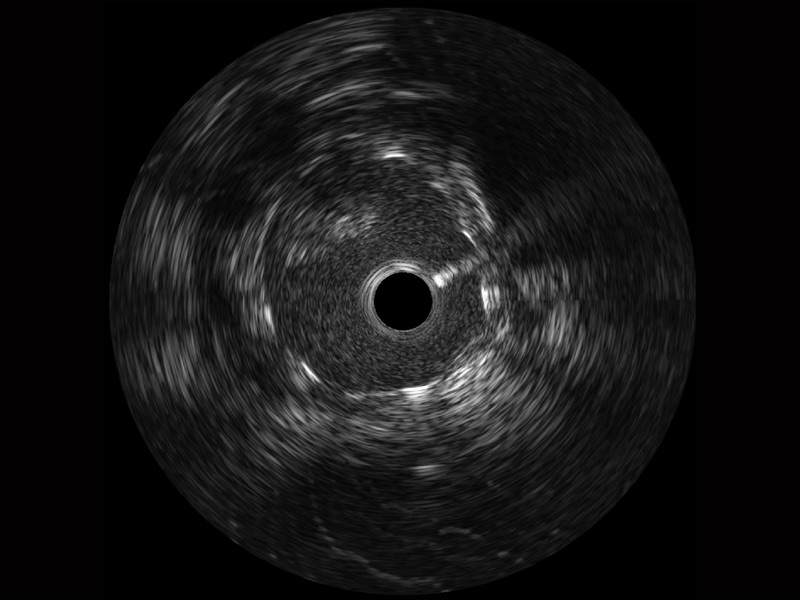

传统IVUS图像

对比传统IVUS导管成像,环球UG官网宽频IVUS图像的近场支架梁显影更细腻,远场中膜外血管仍清晰可辨,兼顾远中近,兼顾分辨力与穿透深度